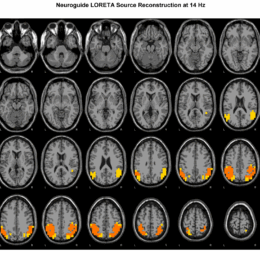

LORETA MESSUNG

Viele Störungsbilder treten mit ähnlichen neurophysiologischen Ätiologien in Erscheinung, aber eben nicht immer mit den gleichen. Um genauer sagen zu können, wo und in welchem Umfang mögliche Fehlfunktionen bei dir vorliegen, können wir auch präzisere Hirnareale analysieren und tieferliegende Strukturen sichtbar machen. Wichtig ist hier allerdings zu erwähnen, dass EEG apikale, also nahe dem Kortex liegende, Neurone ableitet, je tiefer man als0 geht, desto ungenauer ist eine Messung mit dem EEG und desto mehr Werte werden durch Interpolation berechnet.